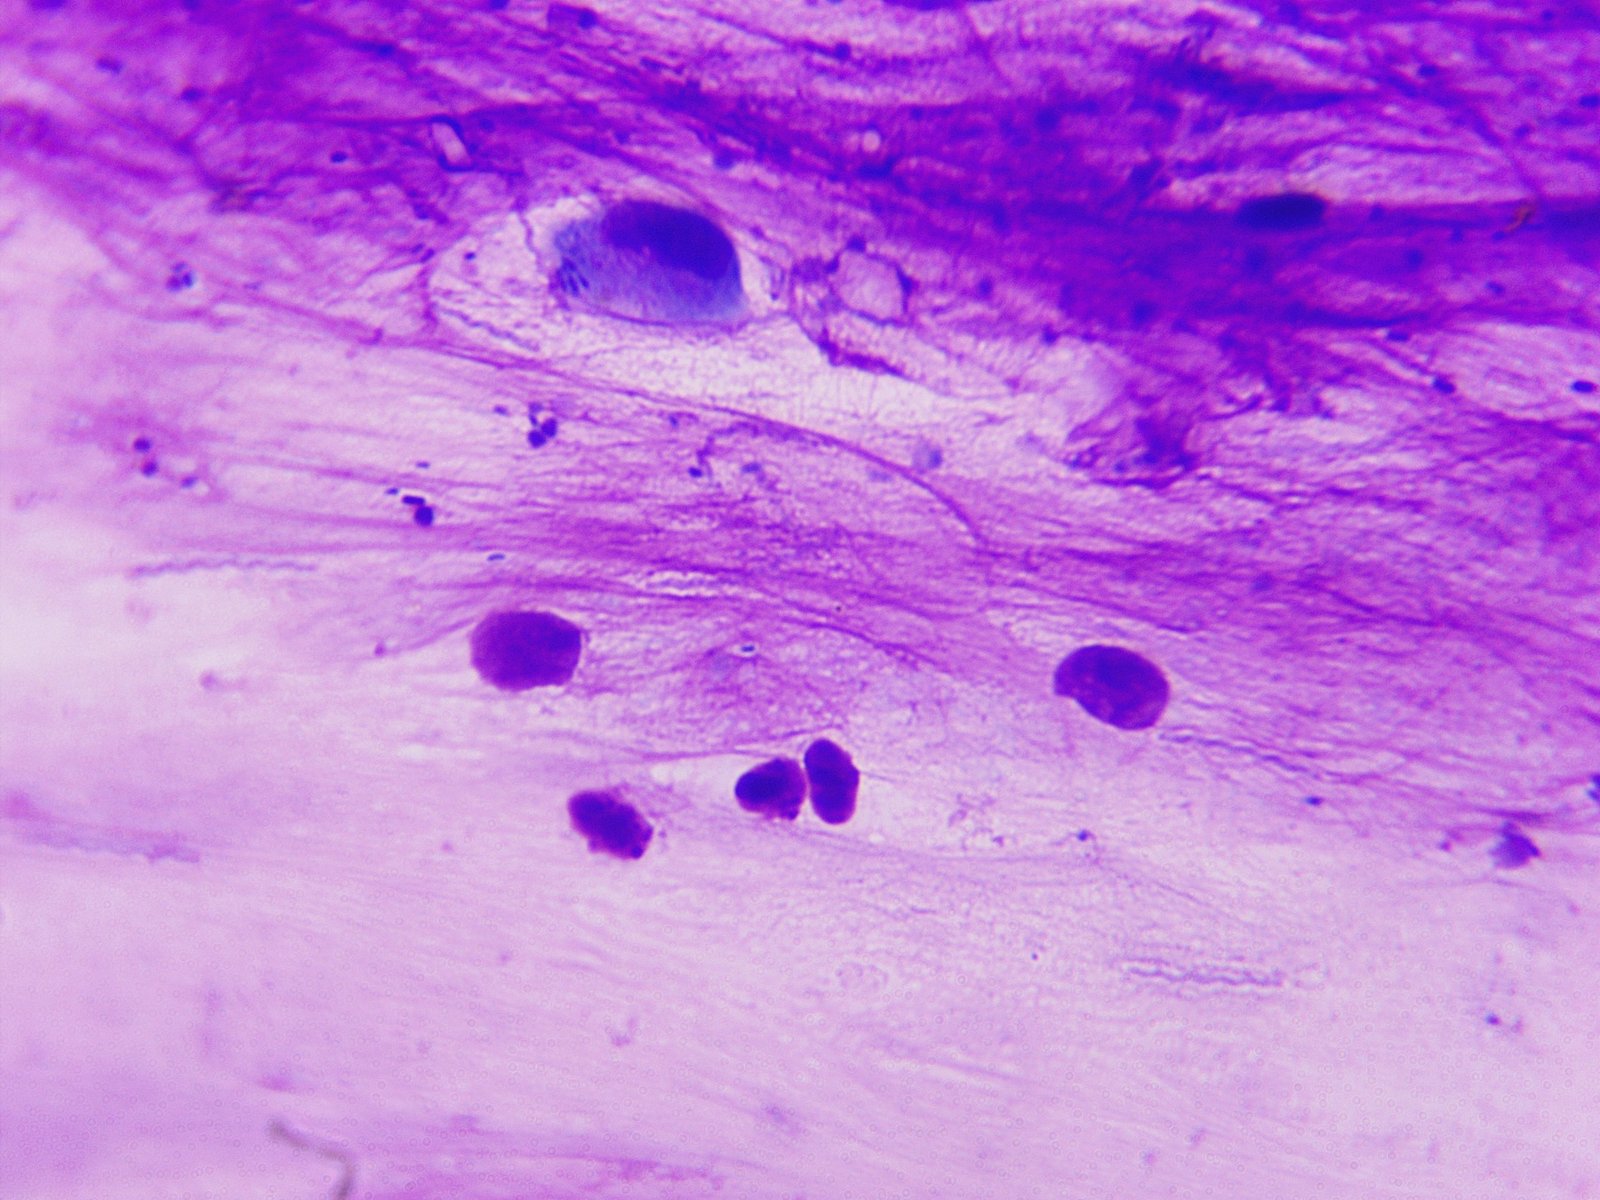

@Zosia , посмотрите, пожалуйста, фото анализа (мазок из клюва). Сдавала цитологию в чел.лаборатории. В заключении написано : "найдено элементы дрожжеподобных грибов, густо кокковую флору (стрептококки, стафилококки)." Лаборанты сказали, что еще что-то есть, но они не знают, что это...Точно, не трихомонады.  Может, Вы по фото увидете.

изображение_viber_2020-06-23_13-12-23.jpg